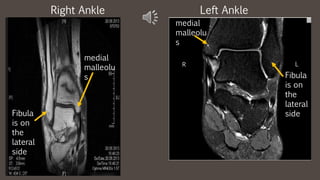

Left AnkleRight Ankle

medial

malleolu

s Fibula

is on

the

lateral

side

R L

s

Fibula